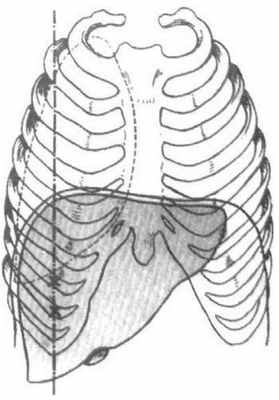

На рисунке изображено печеночные сегменты, фронтальный вид.

- На нормальной фронтальной проекции VI и VII сегментов не видно, поскольку они расположены более кзади.

- Правая граница печени формируется из сегментов V и VIII.

- Хотя сегмент IV является часть левой доли, он расположен правее.

Печень занимает правое подреберье, собственную надчревную и сво-ей левой долей частично левую подреберную область.